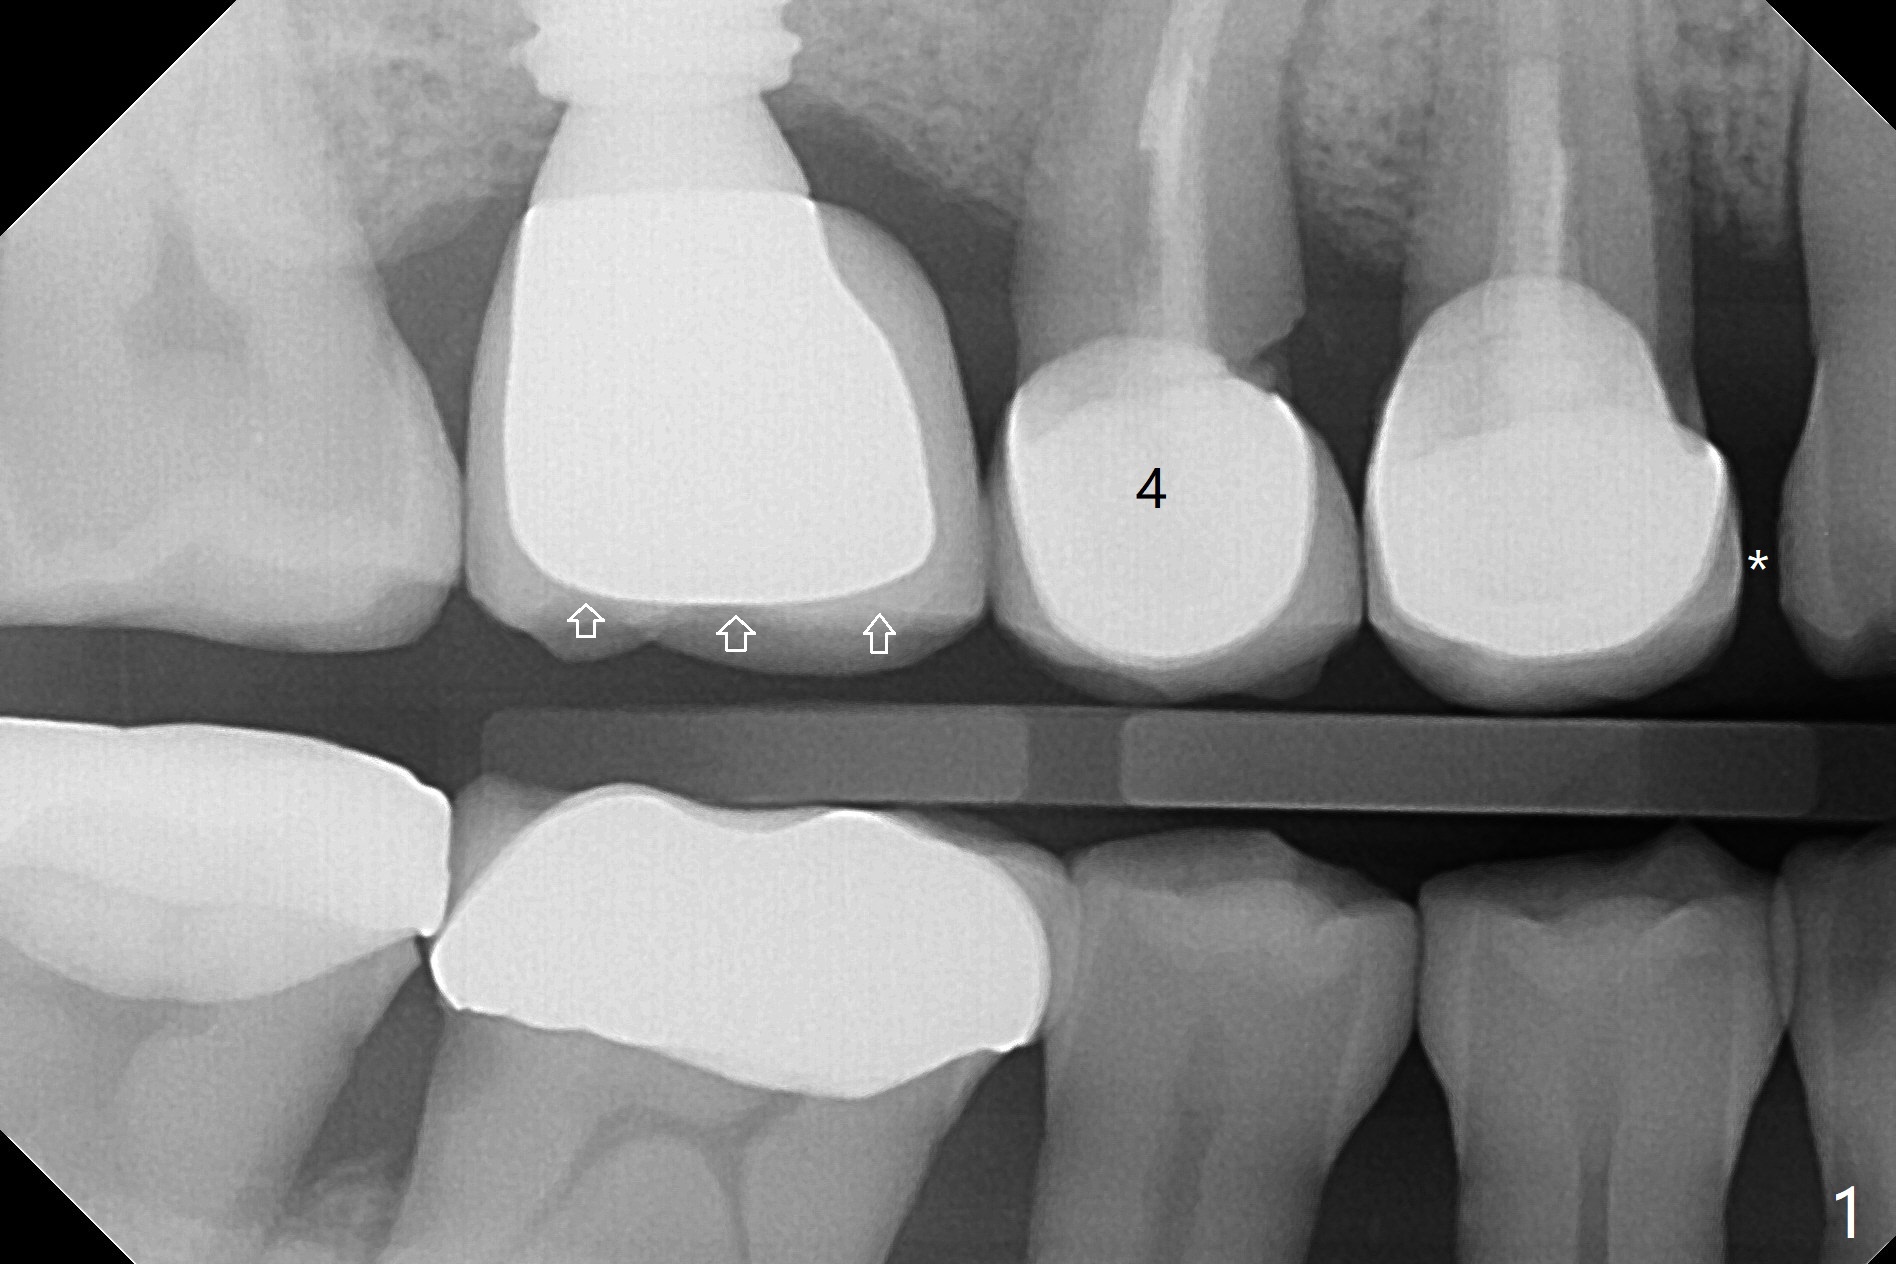

Crown/Implant Ratio

A 53-year-old man has signs of bruxism (Fig.1 diastema *) and root fracture or RCT failure at #4 (Fig.4 (large PARL *)). The RCT failure is related to overload of the affected tooth, which is in turn partially due to infraocclusion of the neighboring implant crown (Fig.1 arrows (implant positioning not ideal)) and partially to due to partial edentulism (Fig.2 missing teeth #14 and 18). For long term, limited ortho will be performed to upright and distalize the tooth #15 (Fig.3 arrow), followed by implants at #14 and 18. For now, the tooth #4 will be extracted (Fig.5), followed by osteotomy in the distal slope of the socket with guide (Fig.6 to get good trajectory). To place a bone-level implant (Fig.7 green), an abutment (blue) with long cuff (pink) is to be used. With poor implant/crown (white) ratio, stress occurs at the junction of the implant/abutment (red arrow), resulting in easy abutment screw loosening. In contrast, stress may be applied to directly to a tissue-level implant (Fig.8 arrow) with less likelihood of abutment screw loosening. The implant/crown ratio improves by approximately 5.5 mm. The roots of the teeth #15 and 16 are so close to each other that interference may occur when the tooth #15 is being uprighted (Fig.9). The empty socket of the tooth #4 is wide buccopalatal (Fig.10); the buccal plate is resorbed coronally (Fig.10 <) so that a 4.5 or 5 mm diameter implant should be placed palatal (Fig.11). Use sticky bone to repair the buccal plate defect and PRF membrane or plug for sinus lift. Following #15 uprighting and distalization, a 5x10 mm implant will be placed at #14; the ridge is triangular (Fig.12 <) so that bone trimmer is needed. A 10 mm long implant will be placed at #18 (Fig.14) to avoid perforating to the submandibular fossa (Fig.13 *).